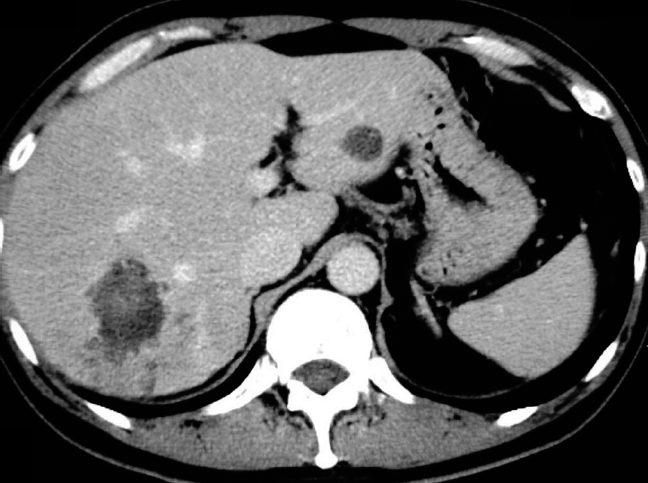

52歳男性。5年前から続く右側腹部痛が悪化し受診。CTで巨大な肝腫瘤(図1)を認め、切除した。その後聴取すると、北海道に居住歴がある。

図1 図1 本症例における腹部造影CT